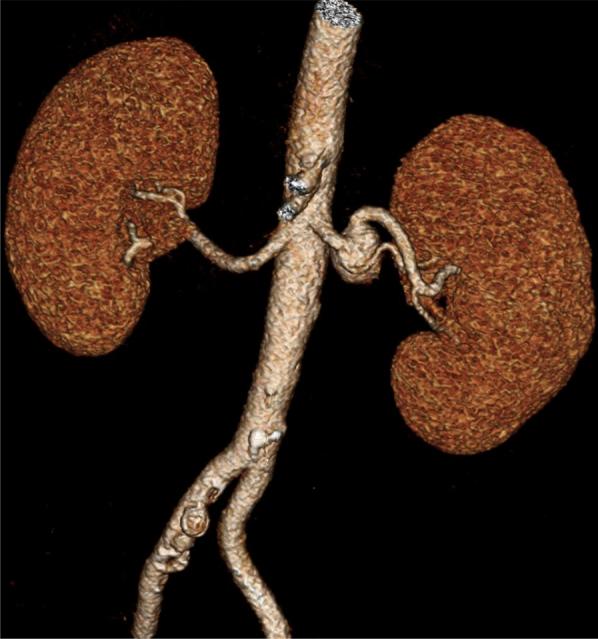

Leber hereditary optic neuropathy is an inherited, rare, mitochondrial metabolic disease that leads to progressive vision loss due to the accumulation of reactive oxygen species. The disorder has been associated with microangiopathy and macroangiopathy. We present a novel case of saccular left renal artery aneurysm in a 27-year-old man with known Leber hereditary optic neuropathy. The lesion was asymptomatic and grew from 1.8 to 2.0 cm during the course of 1 year. We successfully performed an endovascular left renal artery aneurysm repair.

Leber遗传性视神经病变是一种遗传性、罕见的线粒体代谢疾病,由于活性氧的积累导致进行性视力丧失。该疾病与微血管病变和大血管病变有关。我们报告了一例27岁患有Leber遗传性视神经病变男性的左肾动脉囊状动脉瘤新病例。该病变无症状,在1年的病程中从1.8厘米增大至2.0厘米。我们成功实施了左肾动脉动脉瘤血管内修复术。